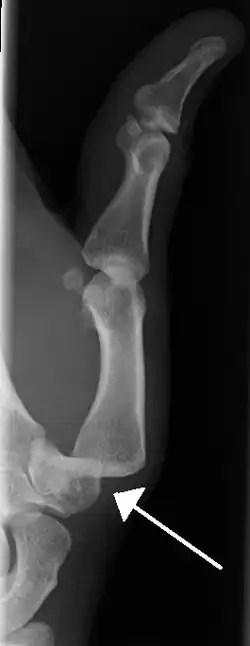

Dislocation of the left index finger -

Radiograph of right fifth phalanx bone dislocation -

Radiograph of left index finger dislocation

Dislocation of the carpo-metacarpal joint.